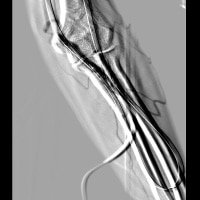

術中のリアルタイムDSA(オプション)

最大7.5fpsの高速リアルタイムDSAが可能です。シャント造影にも対応できます。

動きによる影響を受けないRSMフィルタ処理

造影時に体動などでミスレジが起こった場合、RSMフィルタ処理を行うことにより動きに影響されない画像を作成できます。

血管を流れる造影剤を追跡しながら確認したいときなどにも有効です。